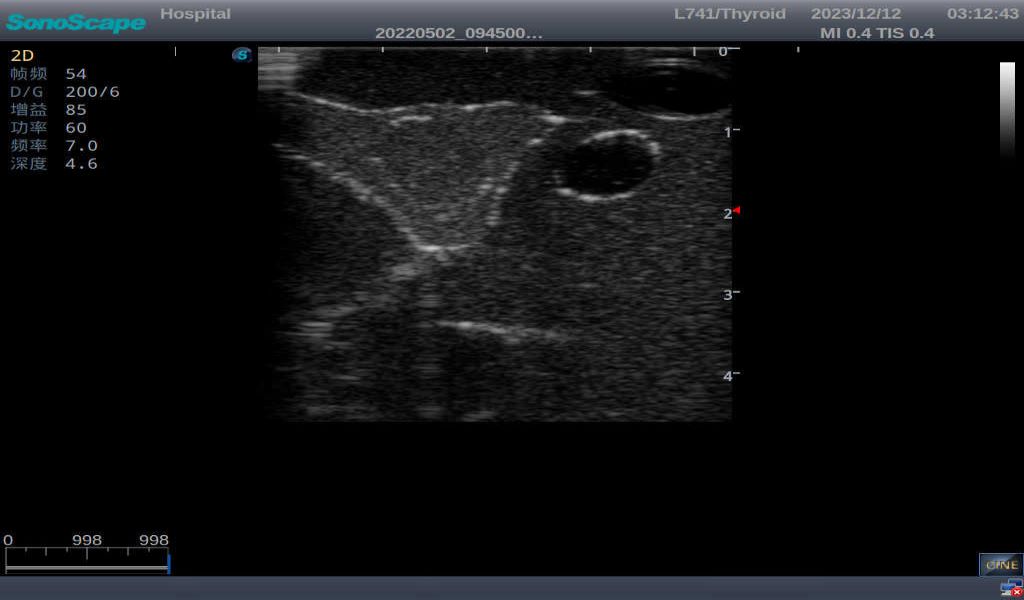

Thyroid adenoma with well-defined border and smooth uniform halo

Thyroid cyst, which fluid area, dark and echo-free area can be seen